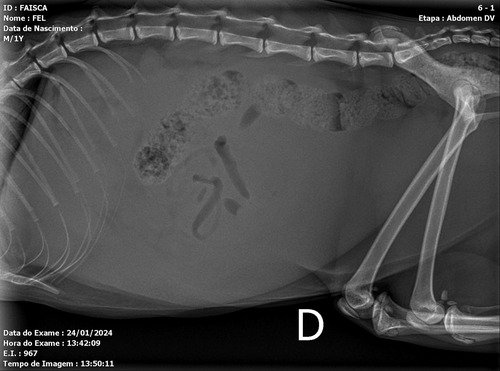

Rx consta líquido e cocô , o liquido impossibilita ver os orgaos